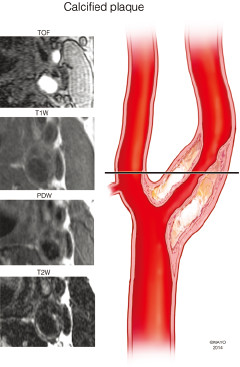

讨论:狭窄率一样,治疗方法就一样吗?

题目:四个患者ABCD去医院体检,都做了超声,发现有颈动脉斑块,且管腔狭窄率基本一样(60%左右),后续又安排做了高分辨核磁,发现A的斑块以钙化为主,B以大脂质核为主,C有斑块内出血,D的斑块已经破裂(如下图所示),ABCD都尚未出现脑缺血症状······

A

1.jpg